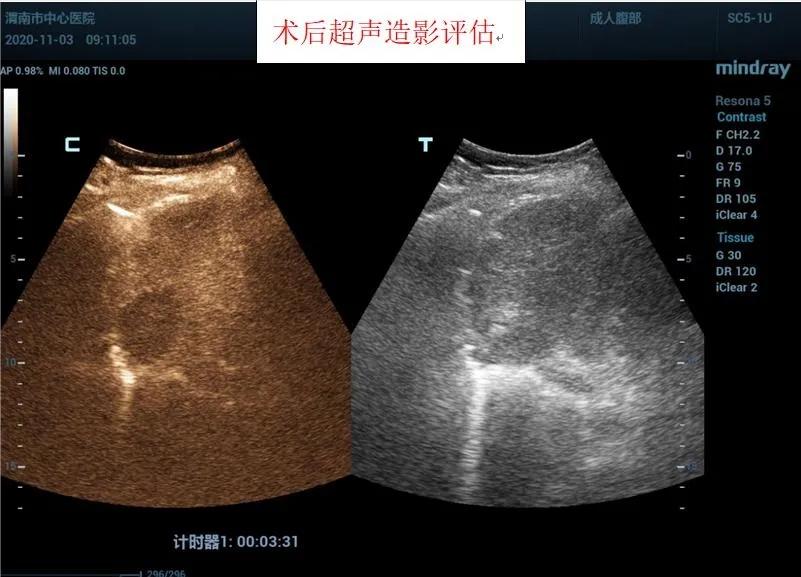

在王建宏教授的指导下,华玺副主任医师、韩婷婷主治医师的默契配合下,经过20余分钟,手术顺利完成,术后安返病房。术后3天超声造影进行评估,显示消融处呈无增强,提示达到预期治疗效果且患者精神状态良好。

据超声科刘晓晖主任介绍,超声造影技术联合微波消融术可以在术前更明确的反映肿瘤病灶的实际大小及其浸润范围,可将微波治疗范围以超声造影测值作为参考,从而更客观的判断肿瘤病灶大小及周围浸润情况,确认需治疗的范围,同时可以使用超声造影在微波消融术中进行检测引导,术后通过超声造影确认肿瘤是否完全灭活。该方法与传统外科手术相比创伤小,手术时间短,术中痛苦小,并发症极少;术后恢复快,缩短了住院时间,乐鱼在线登录入口超声科将超声造影技术与微波消融术联合使用,为患者带来了新的治疗希望。